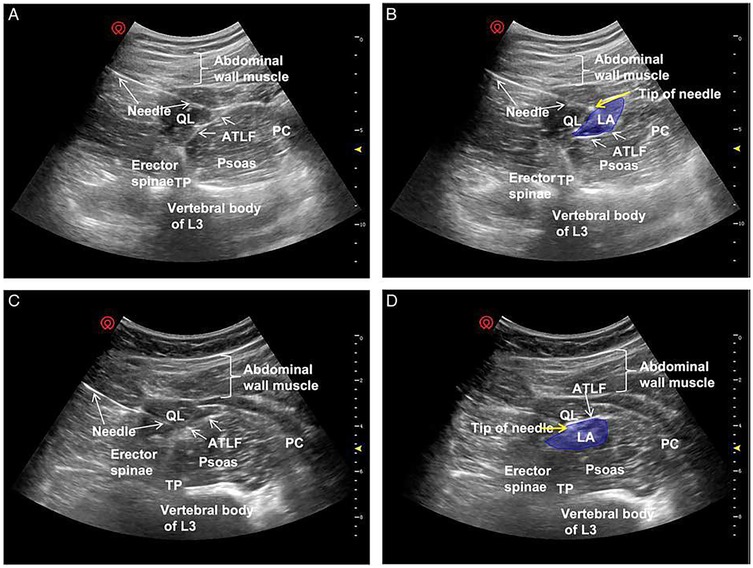

In the conventional transmuscular approach, the patient is positioned laterally. A low-frequency convex probe is placed vertically above the iliac crest. The needle is inserted in-plane from the posterior margin of the probe and advanced anteromedially through the QL muscle (Figure 6a). Ultrasound visualization of the posterior vertebral and paravertebral structures is essential. Once the tip reaches the interfascial plane between the QL and PM, local anesthetic is injected, displacing the PM anteriorly (Figure 6b).

Figure 6

Ultrasound images labeled (a) and (b) showing the anatomical structures. Both images display the quadratus lumborum (QL) and psoas major (PM) muscles. Image (b) highlights the QL with a dashed outline and an arrow pointing towards it. Orientation is marked as anterior at the top and posterior at the bottom.

Figure 6. Ultrasound images of anterior QLB: (a) before injection and (b) after injection. QL, quadratus lumborum; PM, psoas muscle. White arrow: needle trajectory; white dotted line: spread of local anesthetic [Reproduced from Ueshima et al. (28). © John Wiley & Sons, Inc. Distributed under the Creative Commons Attribution License, CC BY 4.0].

Clinical investigations have highlighted differences in anesthetic distribution depending on whether the injection is placed subfascially or extrafascially relative to the anterior thoracolumbar fascia (ATLF) (45). He et al. (45) proposed that the ATLF serves as a barrier limiting anesthetic spread into the lumbar plexus. On ultrasound imaging, the local anesthetic appears as a spindle-shaped hypoechoic area between the ATLF and the QL. With subfascial injection, the QL shifts toward the transducer, whereas with extrafascial injection, the QL displaces the local anesthetic toward the vertebral body (Figure 7).

Figure 7

Ultrasound images showing four panels labeled A to D, each depicting anatomical structures with annotations. Panels A and C display a needle near the QL, erector spinae, and psoas muscles with the vertebral body of L3 identified. Panels B and D highlight the tip of the needle near the QL muscle with a blue area labeled LA. Additional labels include abdominal wall muscle, ATLF, PC, and TP.

Figure 7. Ultrasound images of QLB3. Panels (A,C) show preferred ultrasound landmarks. Panel (B) depicts a subfascial injection of local anesthetic into the ATLF (blue), displacing the QL toward the transducer while preserving PM morphology. Panel (D) illustrates an extrafascial injection (blue), displacing the PM toward the vertebral body with preserved QL morphology. ATLF, anterior thoracolumbar fascia; PC, peritoneal cavity; QL, quadratus lumborum; TP, transverse process; TQL, transmuscular quadratus lumborum [Reproduced from He et al. (45). © Wolters Kluwer Health, Inc. Distributed under the Creative Commons Attribution License, CC BY 4.0].

Subfascial injections demonstrated cranial spread through the ATLF into the endothoracic compartment, effectively blocking lower thoracic nerves, and lateral spread into the transversus abdominis plane, thus providing broader somatic coverage. Importantly, this pathway restricted direct diffusion into the lumbar plexus, thereby reducing the risk of motor weakness. By contrast, extrafascial injections tended to spread along the ATLF, sometimes crossing the 12th rib and extending into potential spaces between the ATLF and the QL. This distribution often reached the lumbar paravertebral region and the PM, increasing the likelihood of lumbar plexus involvement and limb weakness (46, 47).

Patterns of sensory blockade also differed: subfascial injections typically provided coverage from T7–T8 to T12–L1, whereas extrafascial injections extended from T11–T12 to L3–L4 (45). Taken together, these findings suggest that subfascial anterior QLB offers more consistent analgesia while reducing the incidence of undesired motor effects.